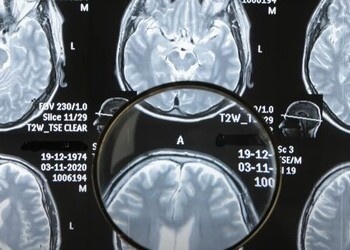

Как алкоголь влияет на работу головного мозга

Алкоголь всегда влияет только негативно на организм человека. Центральная нервная система сталкивается с нагрузкой из-за токсического воздействия спиртного, прямого и косвенного. Расстройства, которые развиваются на фоне злоупотребления этанолом, прогрессируют и постепенно становятся необратимыми, поддающимися только частичной компенсации. Как алкоголь влияет на работу головного мозга — зависит от продолжительности, интенсивности употребления, но при этом воздействие всегда разрушительное. Давайте подробнее узнаем о роли употребления спиртных напитков на появление различных заболеваний нашего рассудка, памяти и в целом личности. Влияние обусловлено органическими причинами. Среди них: Непосредственное влияние этилового спирта, метаболитов вещества сказывается на состоянии нейронов — ткани головного мозга, нервные волокна постепенно отмирают. Дегенерация усугубляется после каждого употребления напитков, но с разной скоростью, интенсивностью. При однократном приёме организм ещё способен в

Алкоголь всегда влияет только негативно на организм человека. Центральная нервная система сталкивается с нагрузкой из-за токсического воздействия спиртного, прямого и косвенного. Расстройства, которые развиваются на фоне злоупотребления этанолом, прогрессируют и постепенно становятся необратимыми, поддающимися только частичной компенсации. Как алкоголь влияет на работу головного мозга — зависит от продолжительности, интенсивности употребления, но при этом воздействие всегда разрушительное. Давайте подробнее узнаем о роли употребления спиртных напитков на появление различных заболеваний нашего рассудка, памяти и в целом личности.